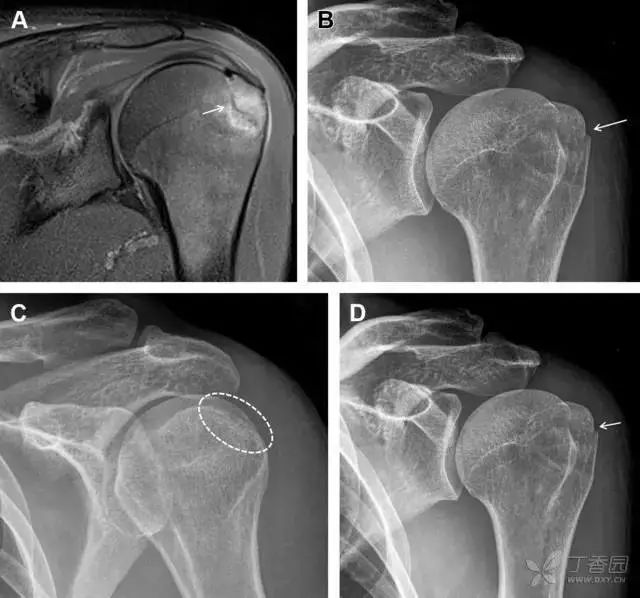

单纯肱骨大结节骨折

与其它肱骨近端骨折不同,单纯肱骨大结节骨折常发生于年轻人。肱骨大结节骨折常由撞击或剪切/撕脱损伤所致:

• 撞击包括直接撞击、肩峰撞击、上关节盂撞击(极度外展时);

• 剪切/撕脱损伤常发生于肩关节前脱位。

在常规前后位片上,大结节与肱骨头重叠,骨折不易发现,外旋位前后位片有助于诊断。

图 1 大结节骨折。(A)脂肪抑制序列斜冠状位 MRI,显示肱骨大结节线性骨折无移位(箭头)与周围骨水肿;(B)外旋位前后位(AP)片,证实大结节骨折(箭头),典型的骨折愈合过程中的骨吸收表现;(C、D)初诊时内旋位、外旋位前后位片,初诊时漏诊,仔细回顾影像,内旋伞下可见双密度影(椭圆),骨皮质中断(箭头)